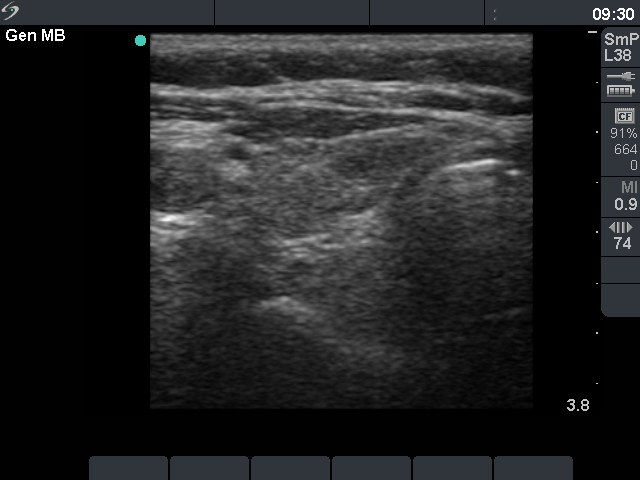

Chronic lymphocytic thyroiditis - Case 79. |

Clinical presentation: a 64-year-old woman was referred for an evaluation of clinical symptoms suggesting hyperthyroidism.

Palpation: no abnormality.

Hormonal investigation: indicated euthyroidism with TSH-level 2.98 mIU/L. Anti-TPO was elevated 306 U/mL.

Ultrasonography: there were small hypoechogenic areas in both lobes. The largest one contained hyperechogenic foci.

Cytology: lymphocytic thyroiditis.